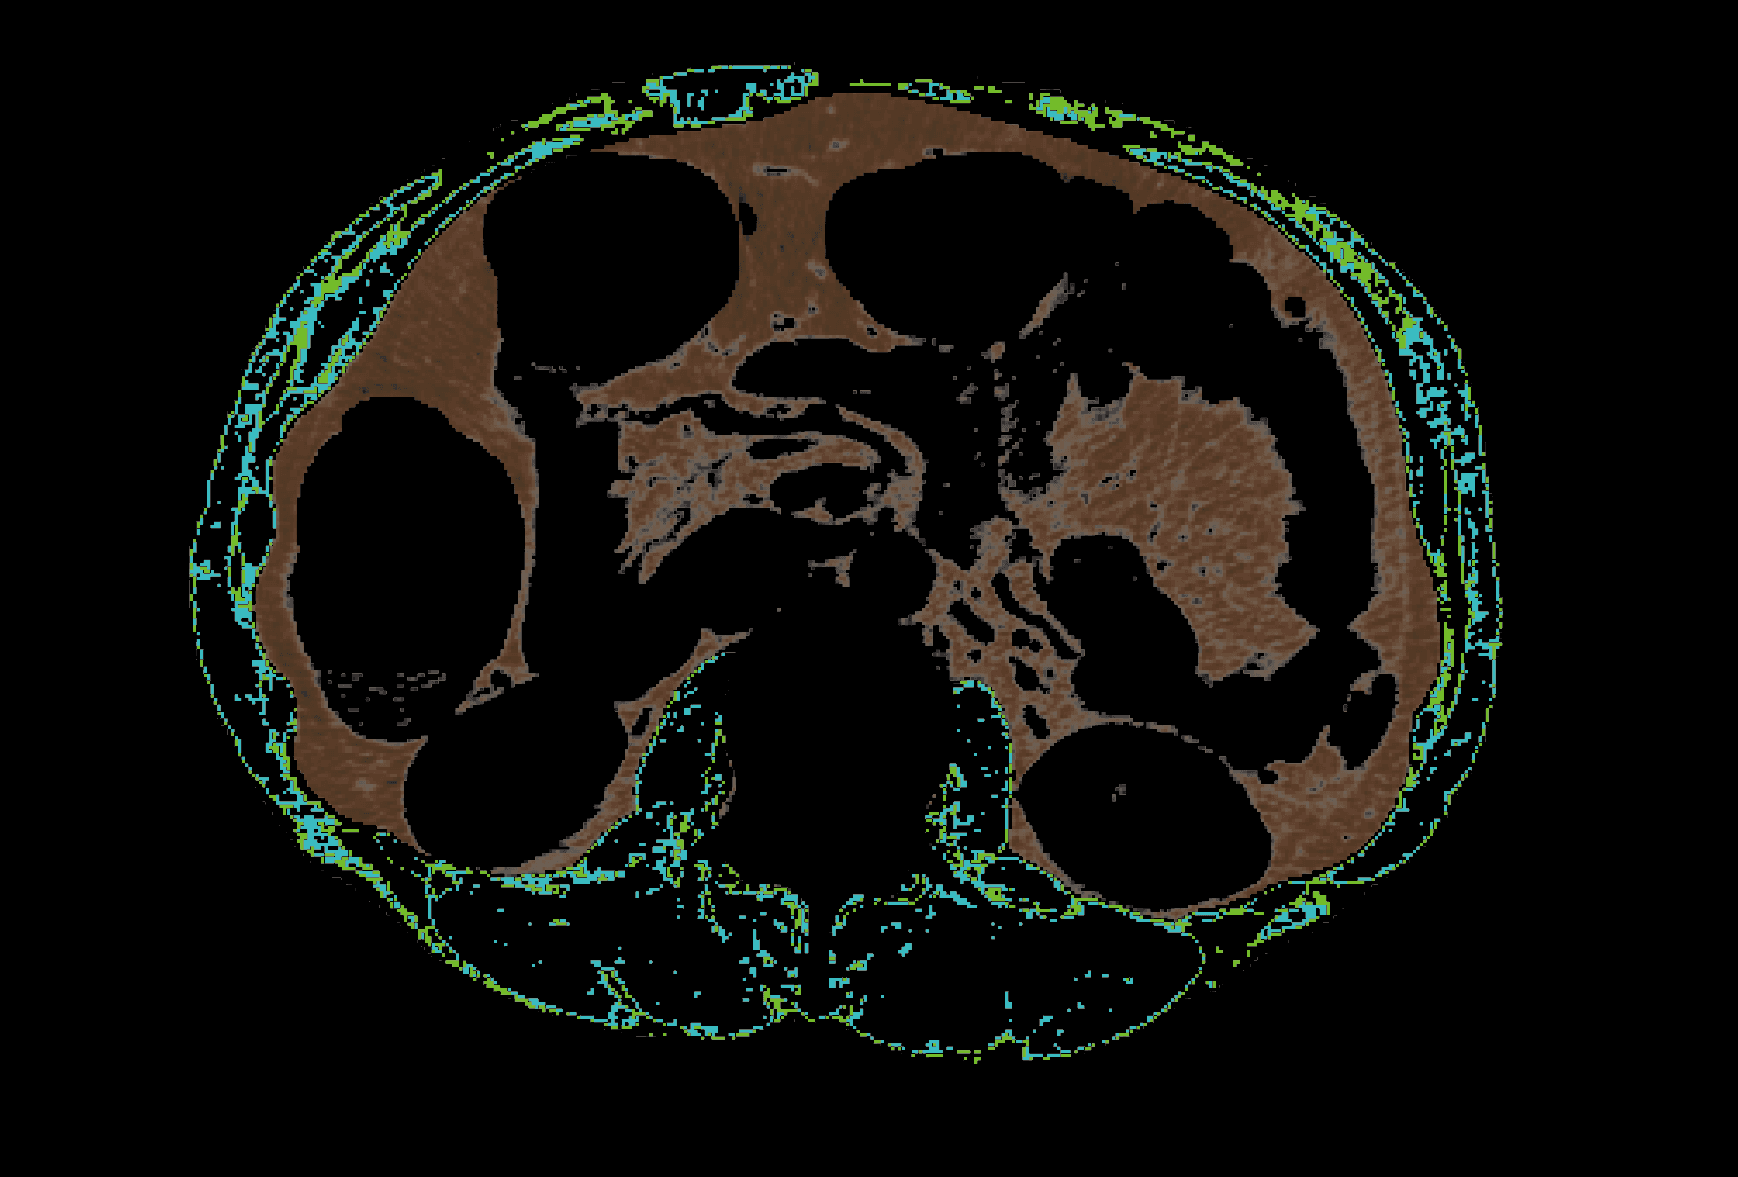

복부 CT 영상에서

근육 및 지방 정보 상세 분석